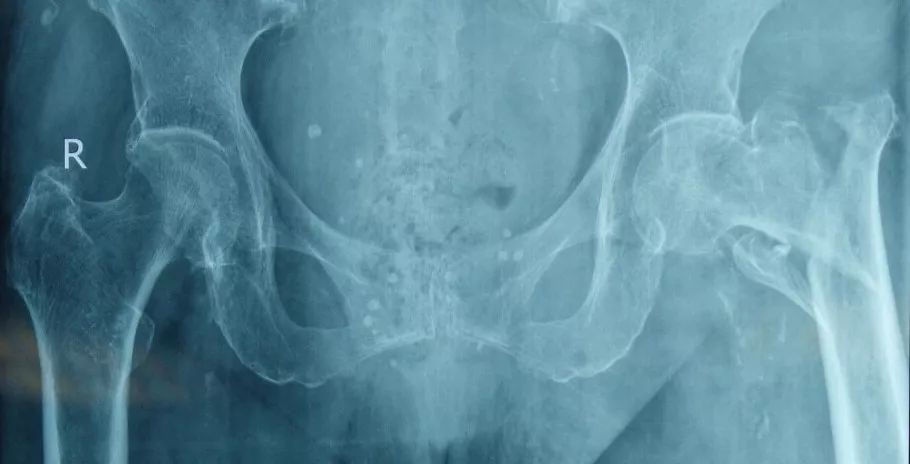

这是一个股骨粗隆间骨折的老年患者,和其他人一样,也是走路时不小心摔倒导致骨折,骨折移位明显,而且有较大的骨碎块。